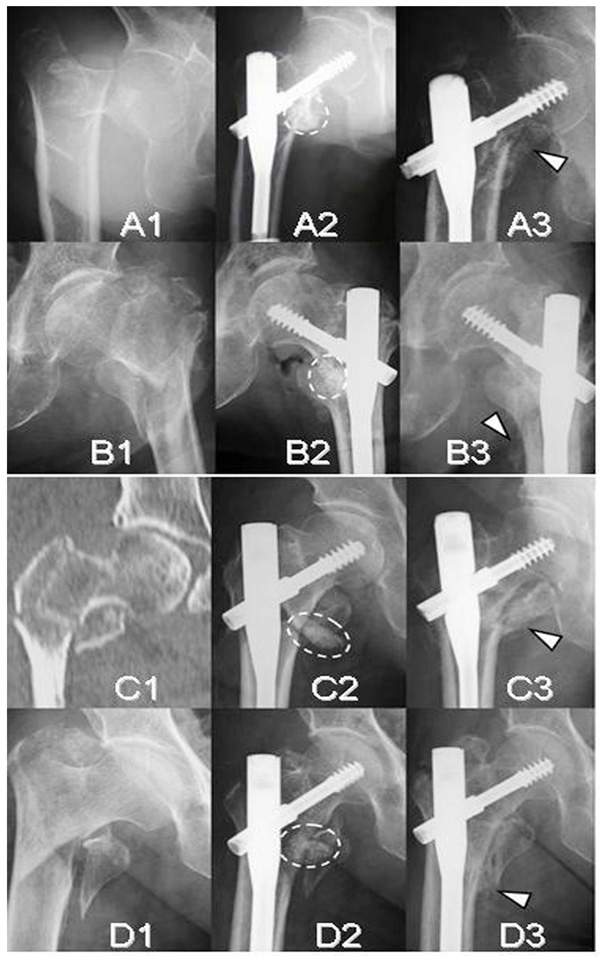

Radiographs and a CT image of four unstable intertrochanteric fracture cases (A;Case 2, B;Case 3, C;Case 4, and D;Case 5). Initial radiographs (A1, B1, C1, and D1). Immediate postoperative radiographs (A2, B2, C2, and D2). Follow-up radiographs at 12 weeks (A3, B3, C3, and D3). Broken ovals indicate the remaining complex of β-TCP granules, hyaluronate, and FGF-2 and arrow heads indicate callus.

CT Evaluation of 3, 8, and 12-week Bone Replacement

At 3 weeks, CT scan images revealed callus formation in only 3 cases. β-TCP granules remained in their original locations and were still visible (Figs. 4A1, 4A2, 5, and 7A). CT scans taken at 6 or 8 weeks showed that most β-TCP granules were resorbed, and new bone formation was found in all cases (Figs. 4B1, 4B2, 5, and 7B). At 12 weeks, β-TCP granules were replaced by bone and marked new bone formation was observed in all cases. Bridging between the shaft and the displaced lesser trochanter was developed in 24 cases. Bridging did not occur in one case due to poor location of the injection (Fig. 7C).